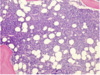

Multiple Myeloma

36

Multiple Myeloma

37

Multiple Myeloma

-bone lesions

38

Multiple Myeloma

-bone lesions, Rouleaux formation

39

Multiple Myeloma

-M spike